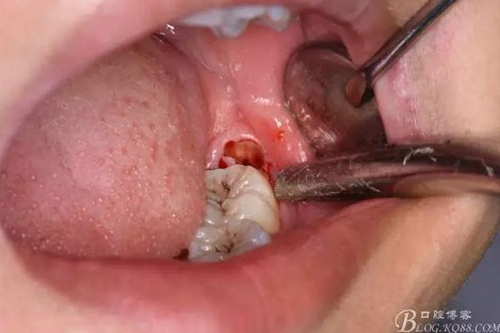

圖2.口內(nèi)可見黃豆大小大遠(yuǎn)中面暴露,擬采用潛掘法分牙

分別取出牙冠、牙根,達(dá)到真正的微創(chuàng)拔牙